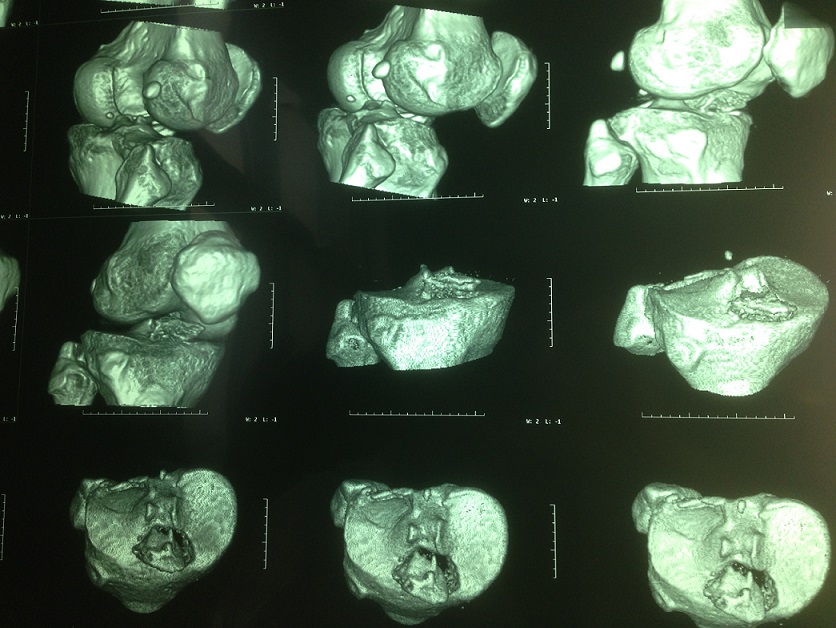

术前患者CT三维重建